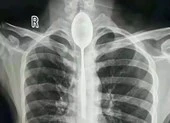

Bác sĩ phẫu thuật ở bệnh viện đã rất bối rối sau khi thấy dạ dày của bệnh nhân lổn nhổn những vật sắc nhọn. Ảnh: SHORTSWORD

Sau khi chụp X-quang, bác sĩ phẫu thuật ở bệnh viện đã rất bối rối khi thấy dạ dày của bệnh nhân lổn nhổn những vật sắc nhọn. Sau đó, các bác sĩ đã yêu cầu bệnh nhân chụp CT.

Trong ca phẫu thuật, các bác sĩ đã mất khoảng nửa giờ để lấy các vật sắt nhọn ra khỏi cơ thể ông Shankar. Hầu hết những cây đinh đều dài khoảng 6,5cm. Rất may những cây đinh này chưa làm thủng ruột bệnh nhân.